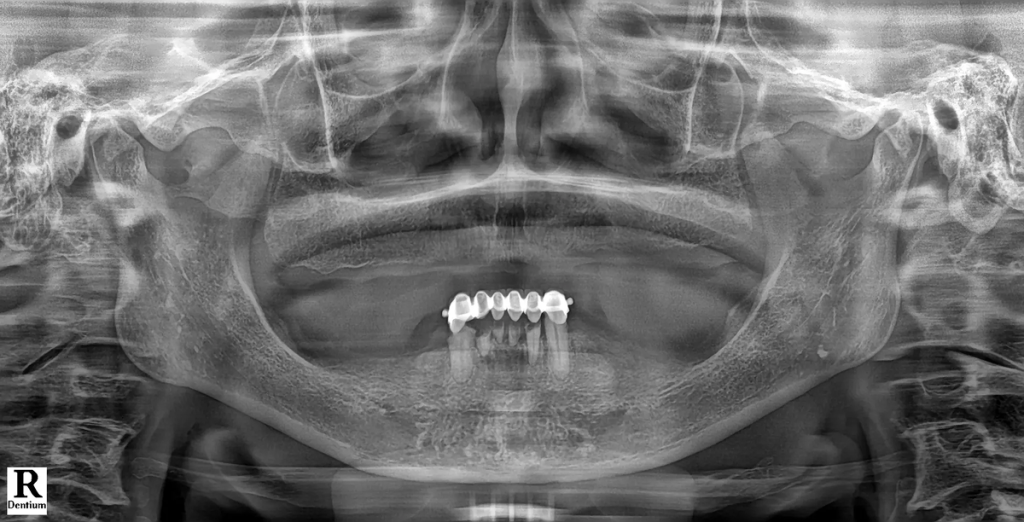

디지털 풀아치 임플란트는 한 턱에 4~6개의 임플란트로 전체 치아 기능을 회복하는 치료입니다. 먼저 3D CT, 파노라마, 디지털 구강 스캐너를 통해 잇몸뼈의 두께·밀도·신경 위치를 3차원으로 분석합니다. 이 단계에서 임플란트가 가능한 뼈 영역과 피해야 할 위험 구간을 명확히 구분합니다.

Case 1. 틀니와 장기 치료가 부담이었던 50대 남성

이 환자분은 여러 개의 치아 손상과 잇몸 약화로 인해 정상적인 저작이 어려운 상태였습니다. 전통적인 전체 임플란트를 고려했지만, 수개월에서 1년 이상 소요되는 치료 기간과 잇몸 절개 수술에 대한 부담으로 치료를 망설이고 계셨습니다. 특히 “잇몸을 크게 절개해야 한다”는 점이 가장 큰 두려움이었습니다.

- 디지털 풀아치 임플란트를 선택한 이유 인터넷 검색을 통해 디지털 풀아치 임플란트를 알게 되었고, 짧은 치료 기간과 최소 절개 수술이라는 점에 관심을 갖고 내원하셨습니다. 상담 과정에서 3D CT와 디지털 스캐닝을 통해 구강 상태를 정밀 분석했고, 임플란트 개수를 최소화하면서도 전체 치아 기능을 회복할 수 있는 구조라는 설명을 듣고 치료를 결정하셨습니다.

- 치료 후 변화 “이제는 음식 종류를 가리지 않고 먹을 수 있어서 삶의 만족도가 확실히 달라졌습니다.” 디지털 스캔 데이터를 기반으로 3D 치료 계획을 수립한 뒤, 컴퓨터 가이드 수술로 임플란트를 정확한 위치에 식립했습니다. 이후 CAD/CAM 기술로 제작된 풀아치 보철물을 장착하며 치료가 진행되었고, 적은 방문 횟수로 치료를 마칠 수 있었습니다.

Case 3. 사고 후 뼈 부족으로 치료를 고민하던 40대 남성

이 환자분은 사고로 여러 개의 치아를 상실했고, 잇몸뼈가 많이 부족한 상태였습니다. 일반 임플란트를 하려면 뼈이식과 긴 회복 기간이 필요하다는 말을 듣고, 치료를 망설이고 계셨습니다.

- 디지털 풀아치 임플란트를 선택한 이유 상담 과정에서 디지털 풀아치 임플란트는 상대적으로 단단한 뼈 부위를 활용해 식립하기 때문에, 광범위한 뼈이식 없이도 치료할 수 있다는 설명을 들었습니다. 디지털 스캐닝과 시뮬레이션을 통해 환자분의 구강 상태에 맞춘 맞춤형 치료 계획이 세워졌고, 이를 바탕으로 치료를 결심하게 되었습니다.

- 치료 후 변화 “치아 때문에 받던 스트레스가 사라졌고, 일상생활로 빠르게 돌아갈 수 있었습니다.” 디지털 가이드를 활용한 수술로 치료가 진행되었고, 생각보다 짧은 기간 안에 치료가 마무리되었습니다. 환자분은 빠른 회복 속도에 만족감을 보였으며,